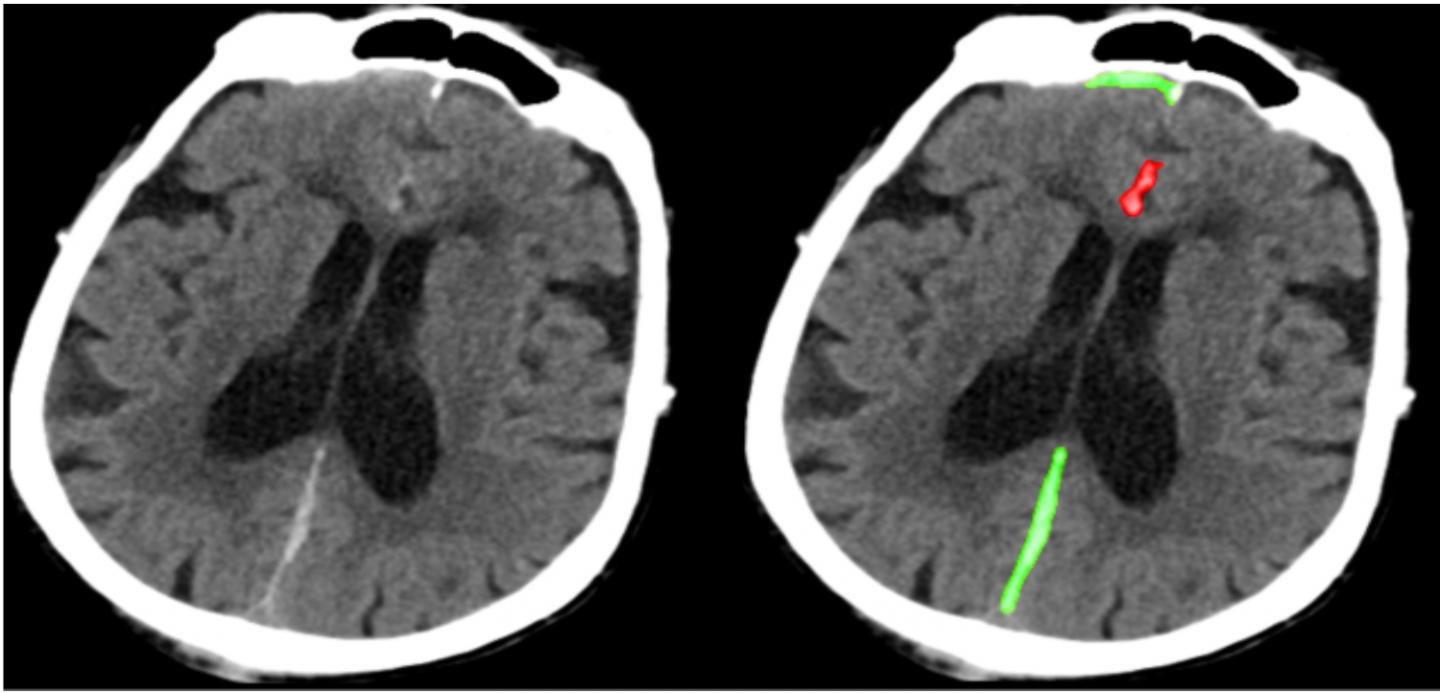

A deep learning algorithm recognizes abnormal CT scans of the head in neurological emergencies such as traumatic brain injury with accuracy similar to highly-trained specialist physicians. The images show the same head CT scan, with the image on the right highlighted to show abnormalities identified by the algorithm. The algorithm also classifies the pathological subtype of each abnormality (red = subarachnoid hemorrhage, green = subdural hemorrhage).

Image courtesy of Weicheng Kuo, Christian H?ne, Pratik Mukherjee, Jitendra Malik, and Esther Lim Yuh